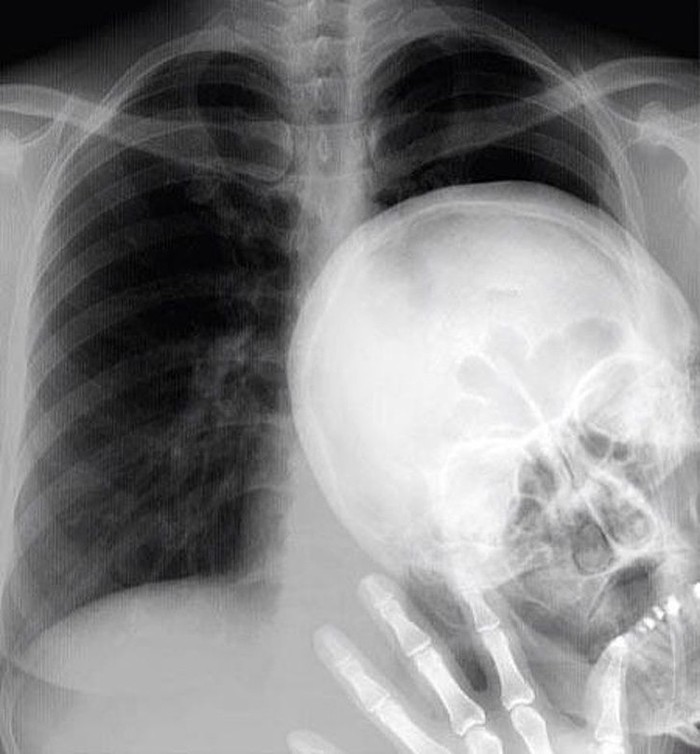

Ini adalah hasil X-ray pertama di dunia, diambil oleh Wilhelm RΓΆntgen pada 22 Desember 1895. (Foto: Brightside)